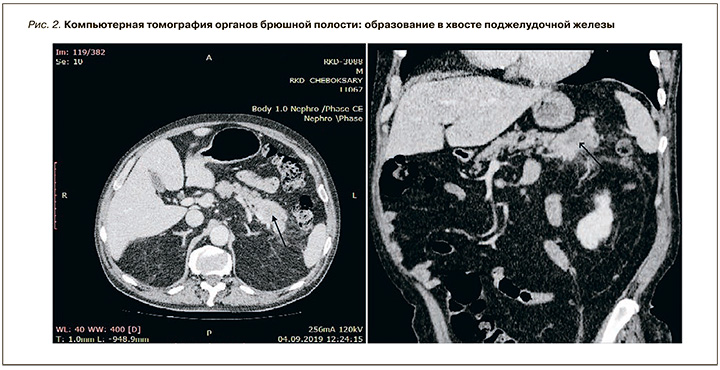

При выполнении компьютерной томографии органов брюшной полости найдено образование в хвосте поджелудочной железы с незначительным накоплением контраста и множественные метастазы в печени без увеличения лимфатических узлов (рис. 2, 3).

С учетом клинико-анамнестических, лабораторных и инструментальных данных пациенту был выставлен следующий клинический диагноз: «двусторонняя тромбоэмболия сегментарных ветвей легочной артерии промежуточно низкого риска на фоне тромбоза глубоких вен нижних конечностей и злокачественного новообразования хвоста поджелудочной железы Т3NXM1. Синдромный (панкреатогенный) сахарный диабет».